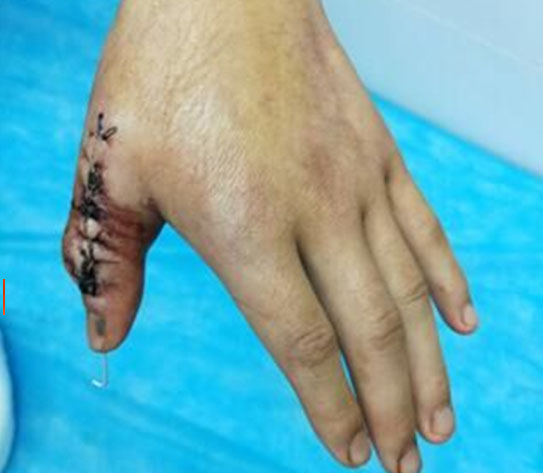

(图为治疗前手术设计)

2018年6月13日,我院创伤外科收治一名多指畸形患者,该患者:男,19岁,因“左手拇指多指畸形19年,伴功能障碍”入院。

我院创伤外科收治这名患者为近节型拇指多指畸形合并三节指骨型拇指多指畸形,为所有类型中最复杂的一种,需要截骨矫形,肌腱及侧副韧带重建,或肌腱移位,手术难度大,对临床医生除要求有丰富的临床经验外,还需要有精湛的手外科技术。在征得患者及家属同意后,创伤外科主任王直强带领科室团队精心策划手术方案,决定给患者实施左手拇指多指切除并功能重建术,手术顺利,术中术后出血少,患者手指功能得到最大限度恢复,解决并指畸形给病人带来的痛苦。

(图为术后一周)